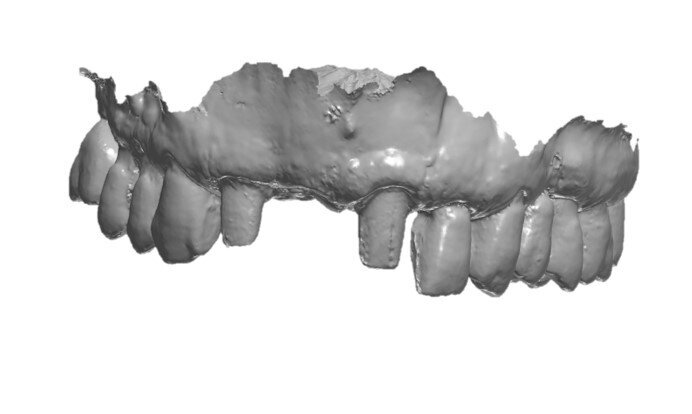

Il paziente era stato precedentemente sottoposto a un intervento di chirurgia rigenerativa con innesto sintetico (stampato in 3D in idrossiapatite/ beta-tricalcio-fosfato) tipo onlay custom-made nella zona dell’incisivo centrale superiore di destra. A 6 mesi dall’intervento, il paziente era pronto a ricevere l’impianto. Per lo studio del caso, il paziente veniva sottoposto a cone beam computed tomography (CBCT) (CS9600, Carestream Dental) (Fig. 1) ed a scansione dell’arcata dentaria di riferimento con potente scanner intraorale (DEXIS IS 3800w, DEXIS) (Figg. 2, 3).

Fig. 2_Scansione intraorale dell’arcata (DEXIS IS 3800w, DEXIS), visione frontale.

Fig. 3_Scansione intraorale dell’arcata (DEXIS IS 3800w, DEXIS), visione occlusale.